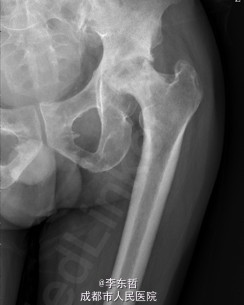

患者男,62岁,因“双髋疼痛4年,加重伴活动受限1年”入院。病员诉入院前4年无明显诱因出现双侧髋部疼痛,行走后疼痛加重,疼痛能忍受,双侧髋部无红肿,皮温不高,无畏寒、发热,休息后疼痛能自行缓解,无夜间疼痛,在当地医院行止痛药内服、理疗治疗,疼痛稍缓解。逐渐加重,1年前双侧髋部疼痛、跛行明显加重,左髋活动受限,行走困难,给予对症治疗症状无明显改善,遂到我科门诊就诊,X线片提示:双侧股骨头坏死,建议手术治疗,故于今日以“双侧侧股骨头坏死”收入我科进一步治疗。

查体:生命体征平稳,心肺腹未见异常;跛行,双左下肢较右下肢短缩1cm,左、右腹股沟中点深压痛,左、右髋叩击痛,左髋屈20°,伸0°,外展10°,内收10°,右髋屈60°,伸0°,外展20°,内收20°。双髋内、外旋活动受限,诱发疼痛,左侧重。 辅助检查:x线片示双侧股骨头坏死、塌陷变形,左侧明显,左髋半脱位。

初步诊断:1、左侧股骨头坏死伴内收肌挛缩(Ficat IV期);2、右侧股骨头坏死(Ficat IV期);3、右膝骨关节炎伴外翻畸形;入院后积极完善术前检查及准备,择期行手术治疗。